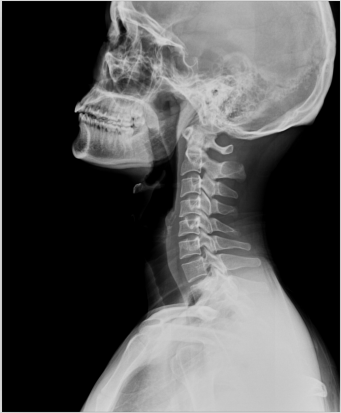

1、外傷骨頭——粗看X光攝影、細(xì)看CT

當(dāng)遇到各種外傷,如果懷疑傷到了骨頭,優(yōu)先選擇X光攝影,檢查結(jié)果快速易得。若要進(jìn)一步觀察,可以選擇CT觀察細(xì)節(jié),甚至磁共振成像觀察隱匿損傷或軟組織損傷。

2、頸椎腰椎——最佳選核磁共振成像、次選CT

頸椎病、腰椎間盤突出等椎間盤疾病需要觀察椎間盤與相應(yīng)的神經(jīng)根,要想更好觀察這些軟組織,最優(yōu)選擇就是磁共振成像。同樣,對(duì)于關(guān)節(jié)、肌肉、脂肪組織檢查,腫瘤、炎癥、創(chuàng)傷、退行性病變以及各種先天性疾病的檢查,磁共振成像也是不錯(cuò)的選擇。CT可以作為觀察脊椎骨質(zhì)增生、椎間孔狹窄的有力補(bǔ)充。